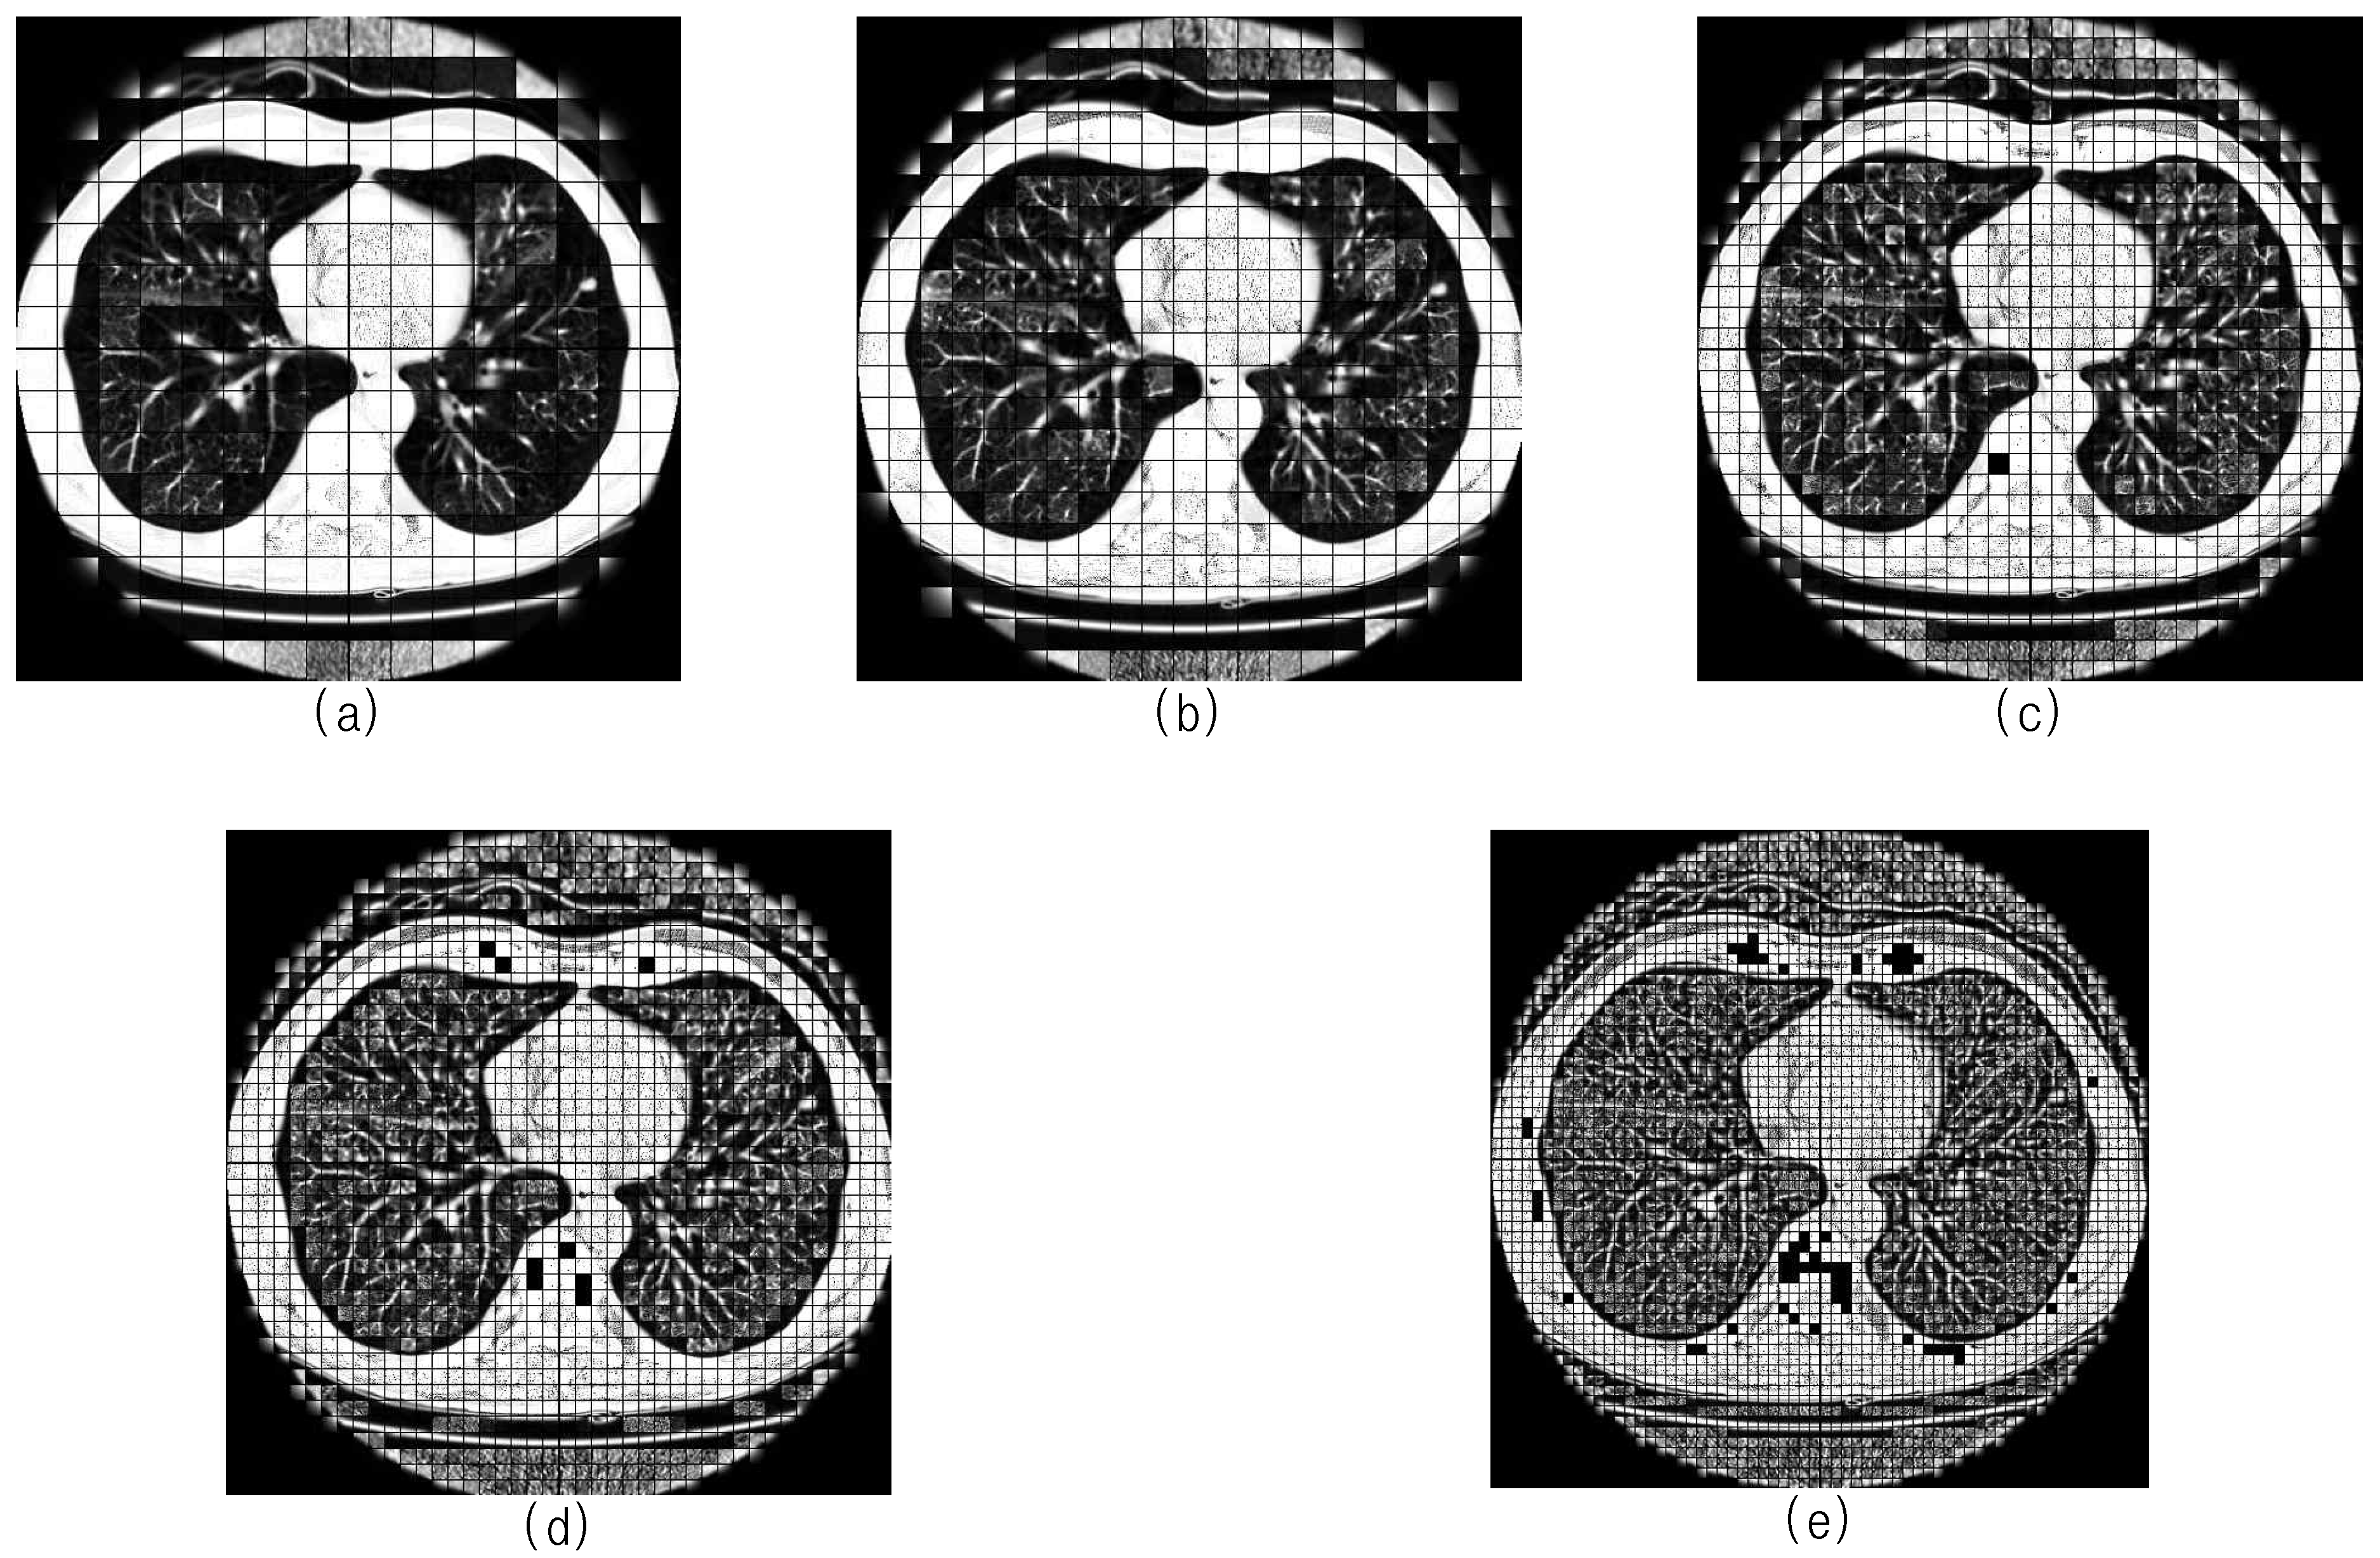

3. Three-Dimensional Block Image Selection Based on Entropy Analysis

4. Nodule Candidates Selection Based on Block Analysis

4.1. Block Image Enhancement

4.2. Block Segmentation and Location Adjustment